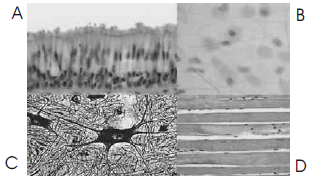

Apesar da complexidade do organismo dos mamíferos, existem apenas quatro tipos básicos de tecidos, que se juntam uns aos outros, em proporções variáveis, para formar os diferentes órgãos e sistemas do organismo animal. Com o auxílio da figura acima, que ilustra quatro tipos de tecidos — A, B, C e D — visualizados ao microscópio de luz, e considerando os métodos de estudo em histologia, julgue o item que se segue.

Para que pudessem ser visualizados em microscópio, após fixação, os tecidos ilustrados na figura devem ter sido seccionados em cortes de 10 a 20 \( \mu \)m de espessura.